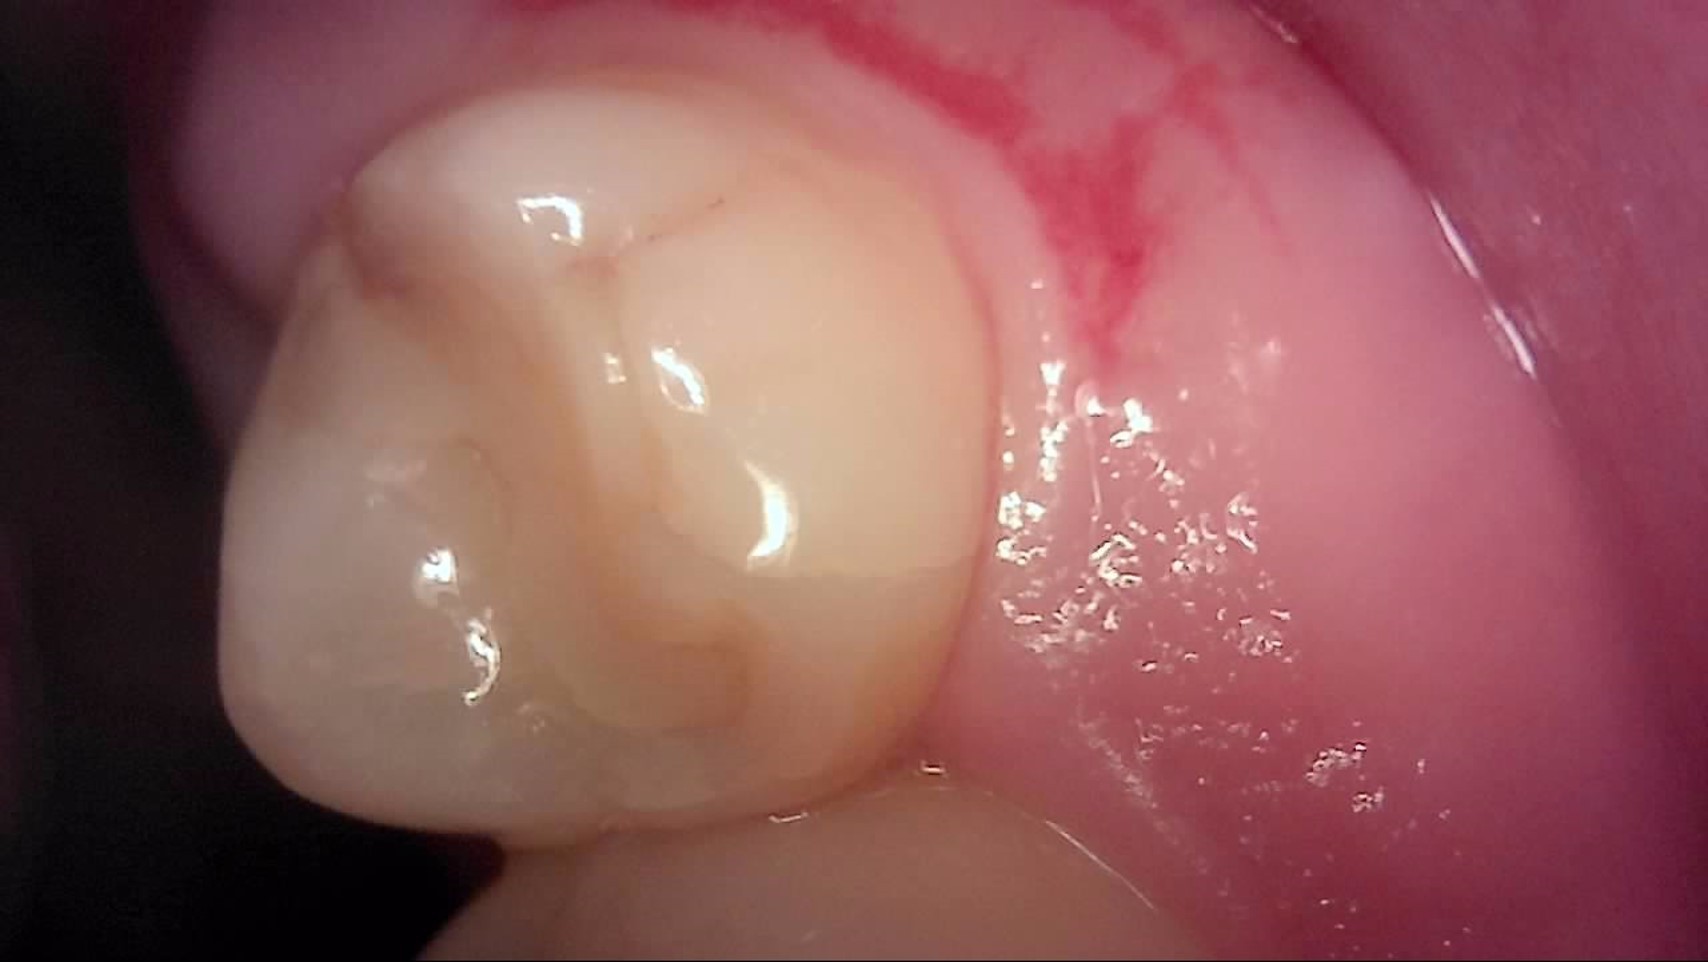

Crack

큐레이캠프로, 큐레이펜씨